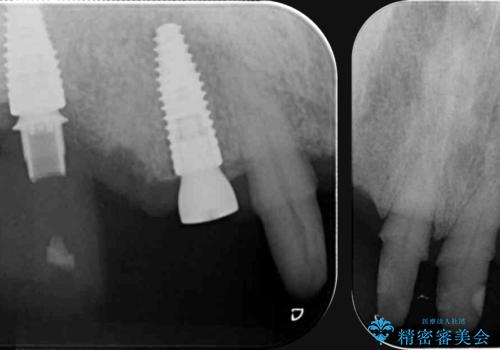

セラミック治療を行う前に歯周病の問題を解決すべく歯周外科を行い歯周ポケットを除去し整備したのちセラミックブリッジ・クラウンの製作を行います。

歯周外科を行ったことで非常に安定した歯周環境となり、引き締まった歯ぐきとなりました。